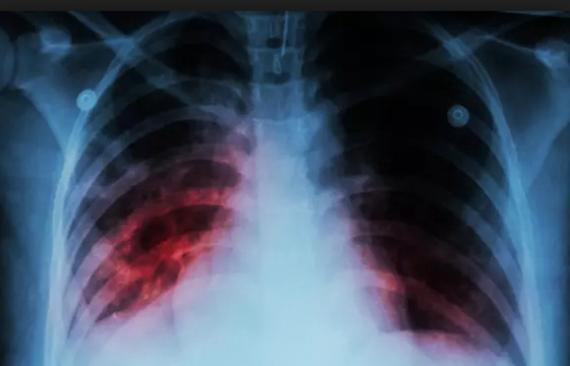

Contenido multimedia principal Tuberculosis, enfermedad silenciosa, pero de cuidado En un año se reportan entre 450 a 500 casos en el Tolima.